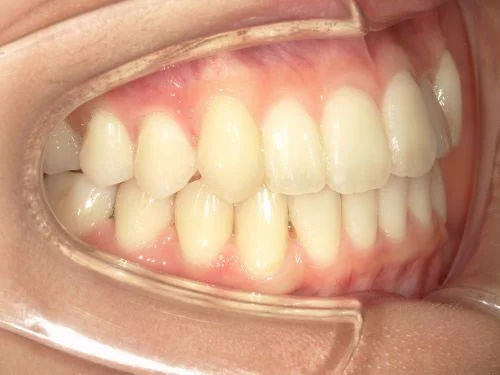

治療前後の写真

<症例2>歯が全体的にガタガタ、出っ歯でお悩み

歯列のアーチがやや狭く、それにより上下の前歯部にガタつきが生じている状態でした。

小臼歯部をわずかに広げてスペースを作ることで、お口元を整えつつガタつきを改善しています。

患者様と症状

主訴:全体的なガタガタ、出っ歯

性別・年齢:30代女性

問題点:上下前歯部の叢生(中程度)、ディープバイト

診断:前歯部の叢生を伴うアングルⅠ級の不正咬合

主なリスク:矯正中一時的に咬合しにくくなる、歯肉退縮

症状:叢生(そうせい) 過蓋咬合(かがいこうごう)

治療内容

治療期間:9ヶ月

治療費用:660,000円(税込)

プラン:26枚コース/モデレートプラン

抜歯:親知らずのみ抜歯

再診治療費:無し

追加治療費:無し

保定装置費:無し